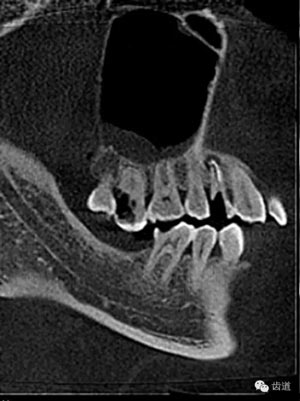

好的開(kāi)始就是成功的一半。通過(guò)CBCT了解根管的位置,形態(tài),方向。

檢查顯示:近頰及腭根充填恰填,遠(yuǎn)頰根管內(nèi)有少許充填物影像。根尖明顯低密度影像。